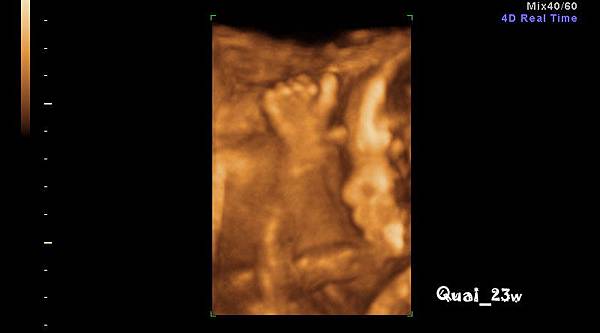

(23w高層次超音波之4D real time)